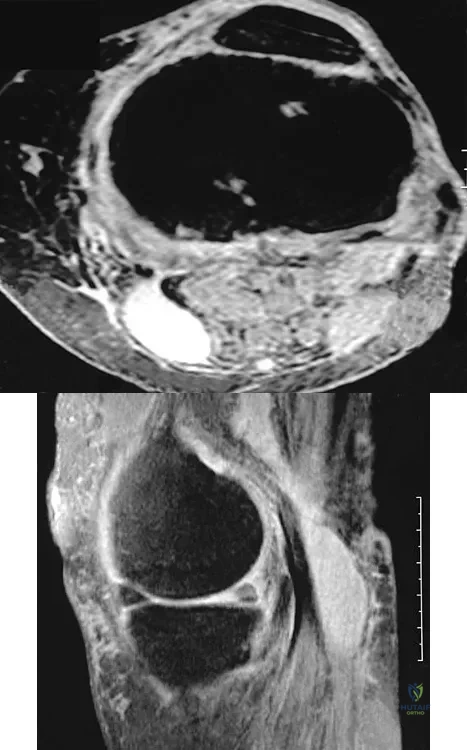

A 51-year-old male truck driver has had progressive left hip pain for more than 2 years, and he reports that the pain has become severe in the past 9 months. He is now unable to work because of the pain. Examination reveals that range of motion of the hip is limited to 95 degrees of flexion, 0 degrees of internal rotation, and 20 degrees of external rotation. The plain radiograph, MRI scan, and intraoperative gross photographs are shown in Figures 9a through 9d. Management should consist of

The diagnosis is synovial chondromatosis. While the plain radiograph fails to show any calcifications, the MRI scan shows an intra-articular mass that involves the capsule. Grossly multiple granular cartilage nodules are seen. Management should consist of removing all loose bodies along with the synovial membrane.